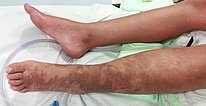

Zu diesem Zeitpunkt 8-jährige Patientin mit verlängertem (+ 1,8 cm) linken Bein, das immer deutlich wärmer ist als das rechte Bein. Am Unterschenkel, Sprunggelenk und Fuß links permanent geringes Ödem, hier als Phlebödem durch den erhöhten Venendruck bei ausgedehnten arteriovenösen Fisteln der gesamten linken unteren Extremität. Purpura Jaune d‘ocre als Einlagerungen von Erythrozyten in der Haut durch Auspressen der roten Blutkörperchen bei chronisch venöser Hypertonie.

Das deutliche Phlebödem des linken Beins mit Schwellung im distalen Bereich bei chronisch venöser Hypertonie durch die multiplen arteriovenösen Fisteln ist im Seitenvergleich gut zu sehen.

Das Bild im 12. Lebensjahr zeigt einen Progress sowohl der Hauterscheinungen als auch des Ödems. Durch die begleitende progrediente Hyperplasie der linken unteren Extremität erscheint diese auch hinsichtlich des Weichgewebes deutlich größer als die rechte Seite.